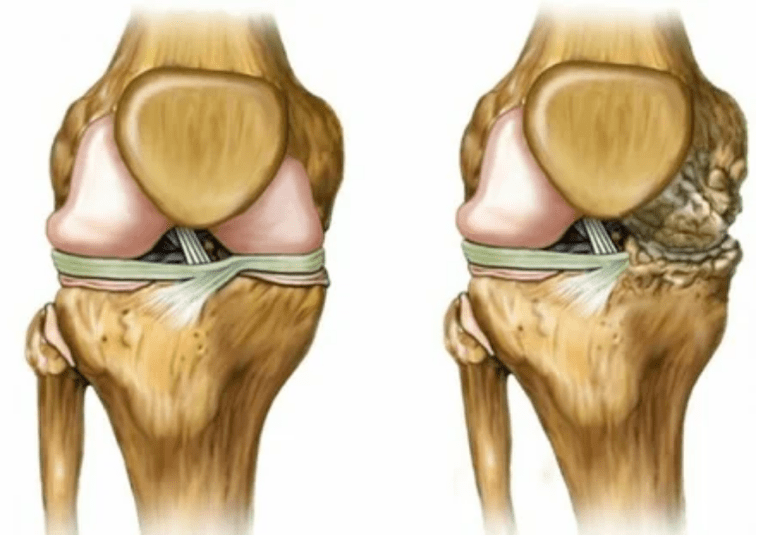

- Decrease in the gap in the jazer compound, which becomes noticeable in the picture.The injury phase determines the diagnostic tantgenologist.Patient feels complexity or inability to completely correct and bend a limb;

- Common deformation, cartilage acquires an irregular form, causing curvature;

- 2. Phase.Due to the lack of supply, the necessary cartridges are destroyed, the surface of the cartilage is formed growth.Pains acquire a more pronounced character, amplifying after a long vacation, eliminated with small physical work.The pain is accompanied by inflammation.Muscles are outstretched, leading to weak or average damaged motor functions.

- 3 degrees.There are often pain, it is difficult to move a limb due to changes in the wrist.The lesions are extensive, become noticeable for a naked look.There was a common place deformation, the affected area of the swollen and becomes red.The line axle is disturbed, leading to the complexity of movement.Pathological changes cause ligament shortening.Subluisha and contracts appear and contracts.The adjacent muscles are shortened or outstretched, from which the contractile function is weakened.